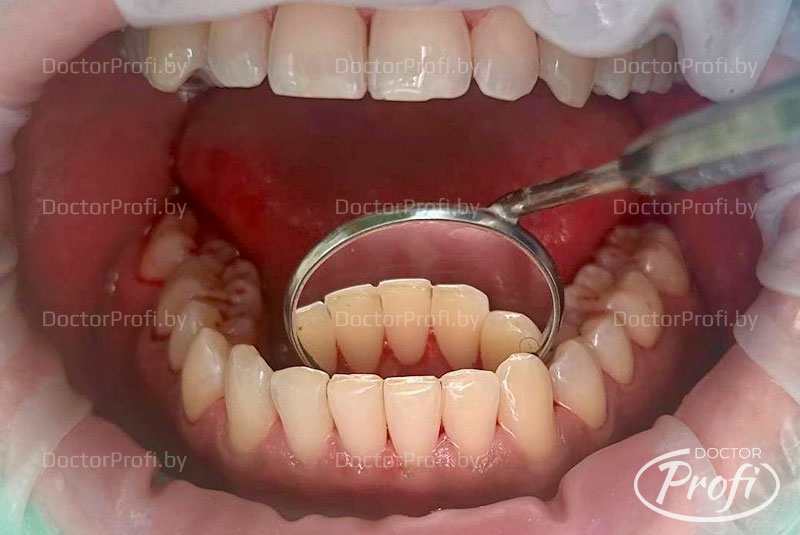

После